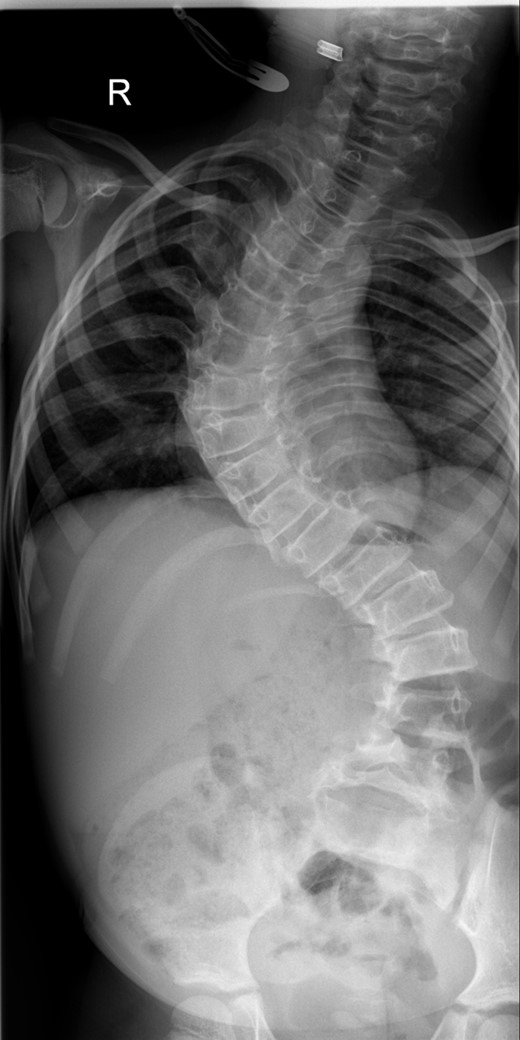

Between the ages of 4 and 6 years, the curve increased rapidly leading to a significant curve measuring 80° in the thoracic spine and 65° in the thoracolumbar spine with a T1–S1 height of 232 mm and T1–T12 height of 150 mm (Fig. 1). A decision was made to intervene operatively and posterior instrumentation with MCGR was performed. Special consideration was given to her bone fragility. Following 4.5 years of bisphosphonate therapy, her last bone mineral density (BMD) assessment by dual energy X-ray absorptiometry before surgery was normal. Her lumbar spine BMD Z-score was +1.5 and the total body less head BMD Z-score was also +1.5. Thus, at age 6 years, a construct of three paired sets of pedicle screws were placed at L2–L4 distally and a combination of pedicle screws at two levels (T4 and T5), with an outer square of sublaminar bands passed under the third and sixth ribs, was placed proximally. The instrumentation used was a 4.5 Expedium System (DePuy Synthes, Raynham, MA, USA) and the Silc Sublaminar Banding System (Globus Medical, Audubon, PA, USA). Post-operative radiographs (Fig. 2) showed good spinal balance and correction of deformity, but fractures of the right 5th and 10th ribs were seen posteriorly at the junction of the rib and transverse process. Following 8 weeks of spinal cast jacket protection, a CT scan showed the rib fractures to have healed. After instrumentation the thoracic curve angle measured 38° and the thoracolumbar curve measured 30°, with a T1–S1 height of 247 mm and a T1–T12 height of 160 mm.

A whole spine radiograph at age 6 demonstrating the double major scoliosis (measuring 80° in the thoracic curve and 65° in the thoracolumbar curve with a T1–S1 height of 232 mm and T1–T12 height of 150 mm).